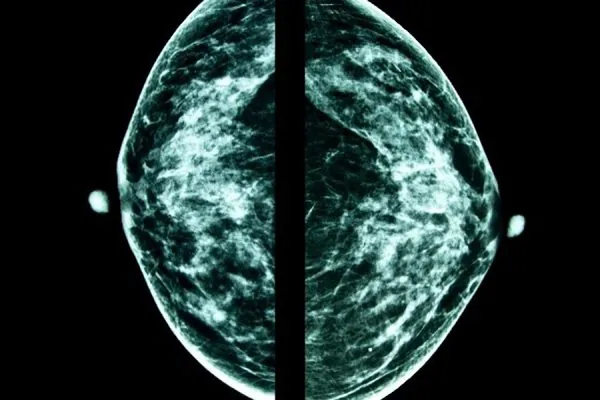

Read more below for cancer prevention tips aimed at helping you minimize your cancer risk, living a healthier lifestyle and knowing when to be screened for different cancers.